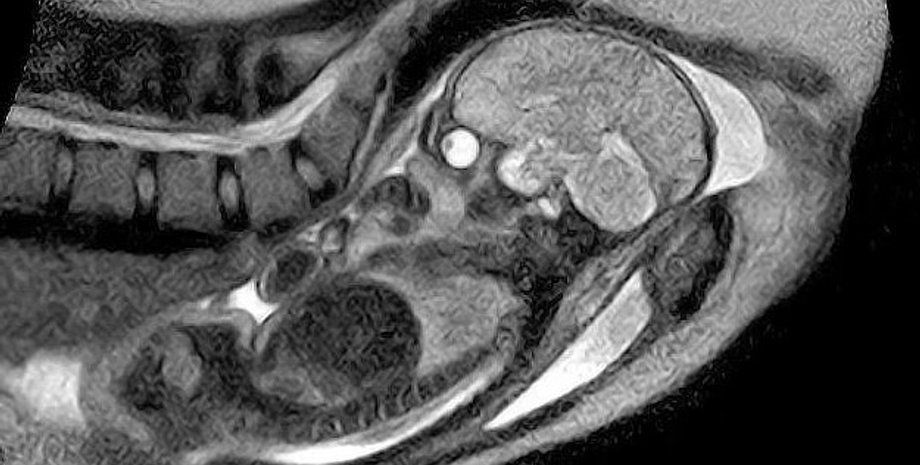

Зазначимо, що МРТ відрізняється від УЗД і потрібно лише в тому випадку, якщо на те є медичні показники матері або дитини. Наприклад, за даними співробітників лікарні Грейт-Ормонд-Стріт, МРТ може допомогти виявити вади розвитку шиї, грудної клітини, черевної порожнини та хребта у малюка ще в утробі матері.

Вчені розповіли, що МРТ використовує магнітні поля та радіохвилі для отримання докладних зображень внутрішньої частини тіла. Наші очі та мозок мають вищий рівень "сигналу" (радіохвиль), а тому виглядають яскравішими й виділяються на зображеннях. Інші частини тіла випромінюють нижчі рівні, а тому здаються темнішими.